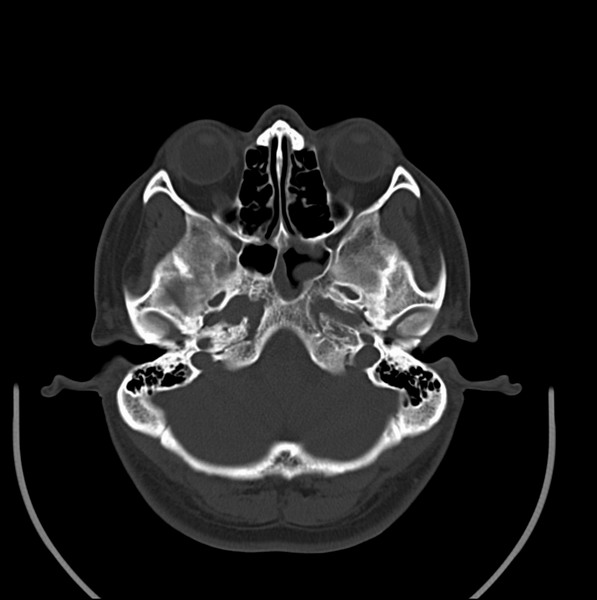

扫描示鼻咽腔不对称,中度狭窄,右侧咽隐窝消失,局部软组织肿块,鼻咽右侧壁增厚形成肿块,突入鼻咽腔,肿块平扫呈等密度,肿块向深部侵润,右侧翼内外肌受侵,右侧咽旁间隙变窄;向后生长,头长肌界线欠清,向后上生长侵犯同侧颈动脉鞘区。双侧海绵窦增宽,内见软组织影与鼻咽部肿块相连。考虑鼻咽癌。鼻咽癌主要是放射治疗,且效果较好;到当地有治疗设备较大医院治疗即可。

鼻咽部新生物(纤维血管瘤?鼻咽癌?)侵犯右侧中颅窝底及右侧海绵窦;建议必要时活检定性。

鼻咽部新生物侵犯右侧中颅窝底及右侧海绵窦,鼻咽癌可能性大。建议增强扫描。纤维血管瘤禁忌穿刺。